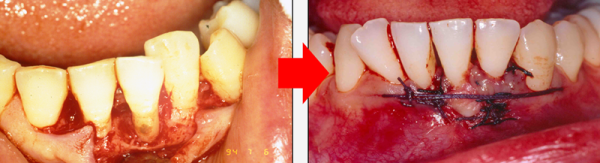

그러나 기존의 치료 방법들은 메스로 잇몸을 절개를 해서 수기구로 치석을 제거하는 방식이라 통증과 회복 기간도 상당하게 발생하는데

더 위험한 것은 잇몸뼈가 공기 중에

노출되면 뼈가 녹는 속도가 훨씬 빠르고

잇몸이 약해지기 때문에 좋은 결과를

기대하기는 어렵습니다.

치료 전과 치료 후는 이렇게 달라집니다.